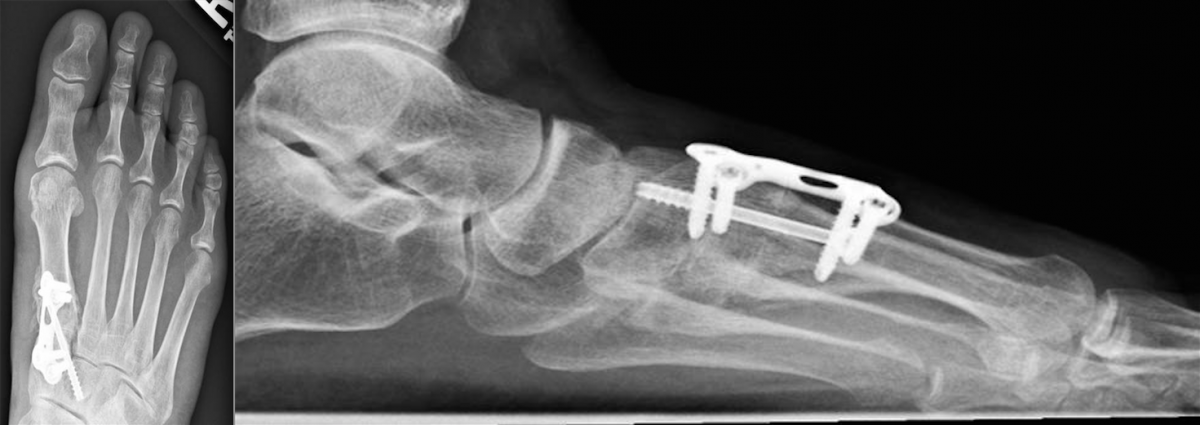

This led to the development of the locking compression plate, which has the ability to preserve the blood supply to bone by reducing periosteal stripping. The traditional plating techniques provided stability by compressing the plate to the bone surface with the screws achieving bicortical purchase as the second point of fixation. However, locking compression plate technology features unicortical locking screws that can be an “internal fixator” that can act as a bridge over compromised bone.8

One of the benefits of locking plates is their ability to be “bridge plates,” whereby they provide excellent axial and angular stability, preserve fragmentary blood supply, and reduce the risk of loss of reduction. Indeed, surgeons do not have to contour these plates anatomically to the bone, and the plates have the potential benefit of providing superior fixation in osteoporotic bone. Indications for the use of locking plates include diaphyseal/metaphyseal fractures in osteoporotic bone, multifragmentary diaphyseal/metaphyseal fractures, osteotomies in at-risk patients (poor bone stock, revisions, etc.), articular fractures, segmental fractures with multiple patterns, and any combination of the above.9

Minimally invasive plate osteosynthesis maintains bone vascularization with minimal periosteal stripping, thus improving bony consolidation and decreasing operative time, complications and infection rates. The application of a locking plate using the minimally invasive plate osteosynthesis technique generally consists of making small incisions proximal and/or distal to the fracture site, percutaneous reduction and subsequent extraperiosteal placement of the plate with any radiolucent percutaneous guide.

Another advancement in the development of locking plate technology is the addition of polyaxial or variable axial screw holes in the plate. This becomes extremely valuable when a surgeon is addressing a periarticular fracture, especially one that involves significant comminution or damage to the soft tissue envelope. These plates were designed to improve angular stability by allowing variable screw trajectory to the plate, thereby increasing the probability that the screw will be able to purchase good bone while avoiding articulating surfaces.